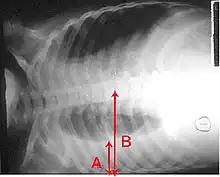

A pleural effusion appears as an area of whiteness on a standard posteroanterior chest X-ray.[12] Normally, the space between the visceral pleura and the parietal pleura cannot be seen. A pleural effusion infiltrates the space between these layers. Because the pleural effusion has a density similar to water, it can be seen on radiographs. Since the effusion has greater density than the rest of the lung, it gravitates towards the lower portions of the pleural cavity. The pleural effusion behaves according to basic fluid dynamics, conforming to the shape of pleural space, which is determined by the lung and chest wall. If the pleural space contains both air and fluid, then an air-fluid level that is horizontal will be present, instead of conforming to the lung space.[13] Chest radiographs in the lateral decubitus position (with the patient lying on the side of the pleural effusion) are more sensitive and can detect as little as 50 mL of fluid. Between 250 and 600mL of fluid must be present before upright chest X-rays can detect a pleural effusion (e.g., blunted costophrenic angles).[14]

Micrograph of a pleural fluid cytopathology specimen showing malignant mesothelioma, one cause of a pleural effusion. A pleural effusion as seen on lateral upright chest x-ray

A pleural effusion as seen on lateral upright chest x-ray- Pleural effusion as seen behind the heart.[17]